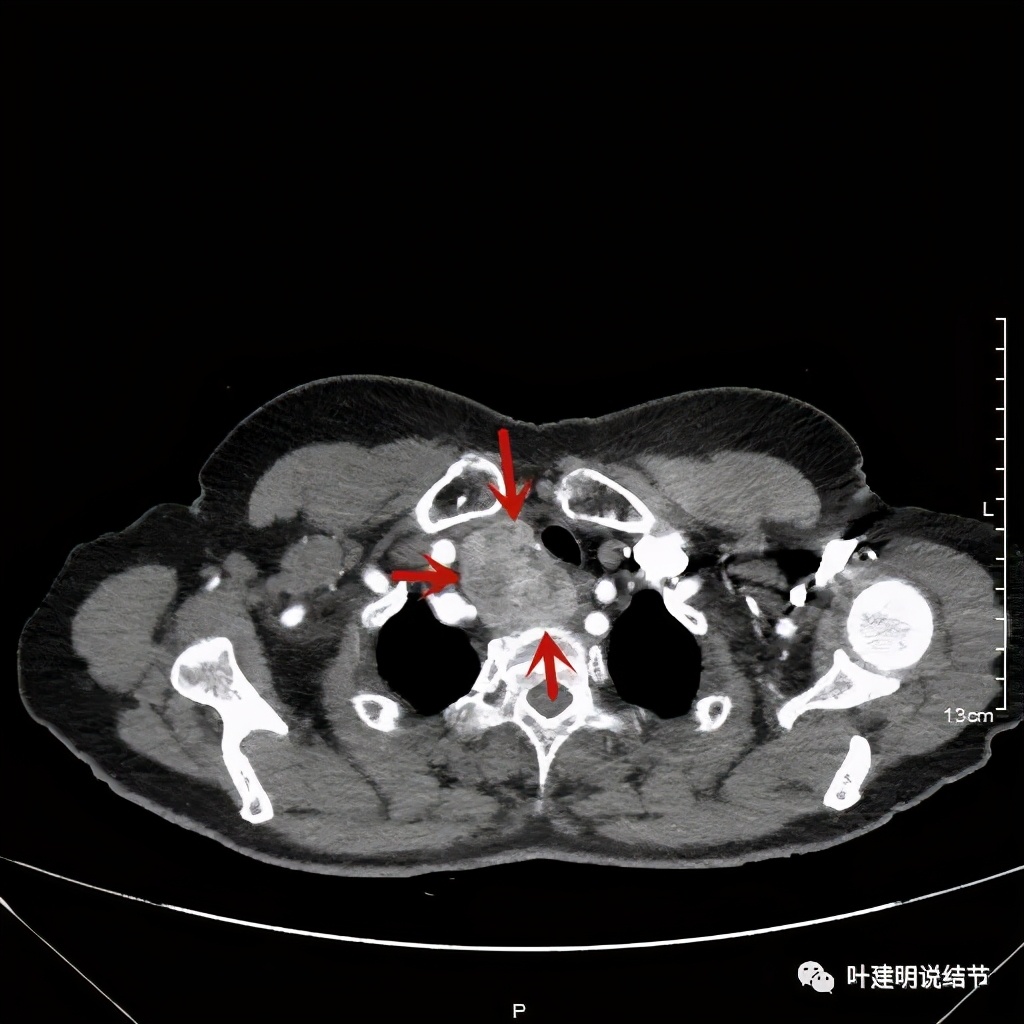

金华地区的某A,今年已经76岁了,近段时间觉得胸闷不适,还有刺激性咳嗽,总是不会好,到当地医院查了胸部CT,发现是纵隔肿瘤。当地医生建议她到金华市中心医院做下气管镜下穿刺活检,以明确肿瘤性质。因为认识我们医院的某外科主任,所以又建议她来找我,结果我一看她从当地带来的片子,是纵隔内巨大的占位,与气管关系密切,位于气管右侧、食管右前侧、上腔静脉左侧、无名静脉后侧,被诸多结构包绕着,而且肿瘤密度不均,靠气管与无名静脉侧间隙不清,首先考虑纵隔内恶性或交界性肿瘤,由于年纪这么大,手术风险较高,若与气管有侵犯,则手术达不到根治,我也觉得应该先行经气管镜下的穿刺活检,明确病理后再考虑怎么办。所以让某A住到呼吸内科去,打算行气管镜下纵隔肿瘤穿刺活检。因当地的片子扫到胸顶部为止,没有做增强,我们先取本院增强片子上达胸顶,下达肿瘤下缘的范围来看看肿瘤的样子:

胸顶就开始有肿瘤了,黄色示受压迫移位的气管,红色示肿瘤